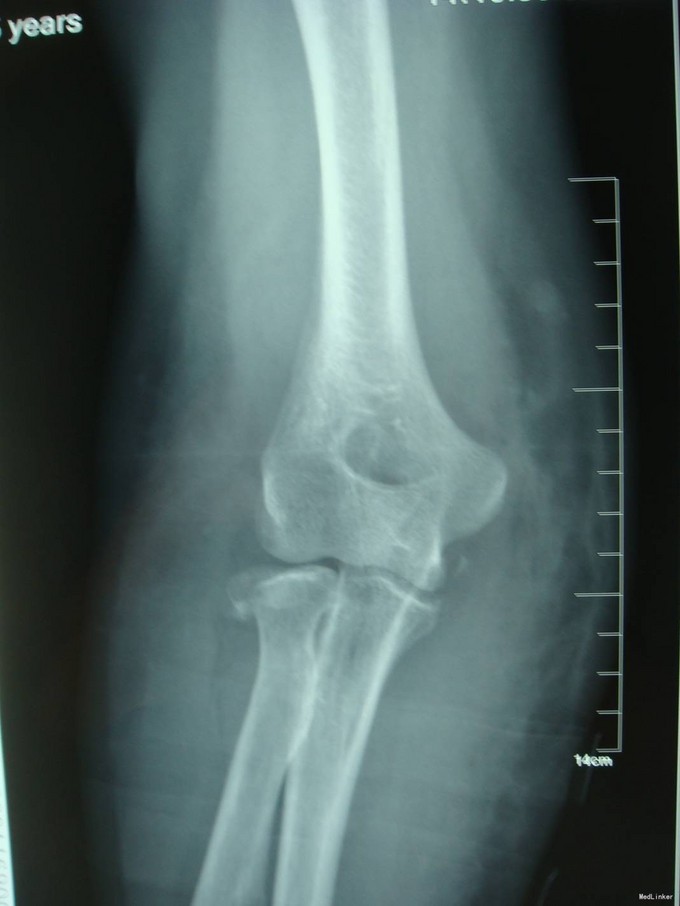

主诉:摔伤后右肘部疼痛10小时 患者自述2014-9-2 早8点自己走路时不小心摔倒,右肘部着地,导致右肘部疼痛、肿胀、活动受限,于当地医院拍片诊断为“右肘关节脱位”,给予手法复位, 为求进一步治疗来我院,诊断为“左肘关节骨折”,并收入我科,患者自受伤以来,无发热,无呼吸困难,无腹痛腹泻,饮食睡眠正常,大小便未见异常。

患者步入病房,左肘关节肿胀明显,压痛(+),骨擦音及骨擦感(+),左上肢感觉未见异常,左手指活动正常,左桡动脉搏动可触及。

患者入院后左肘关节石膏固定,左肘关节对症消肿等治疗。1周后完善检查后查无明显手术禁忌症后行左桡骨小头骨折切开复位内固定术。